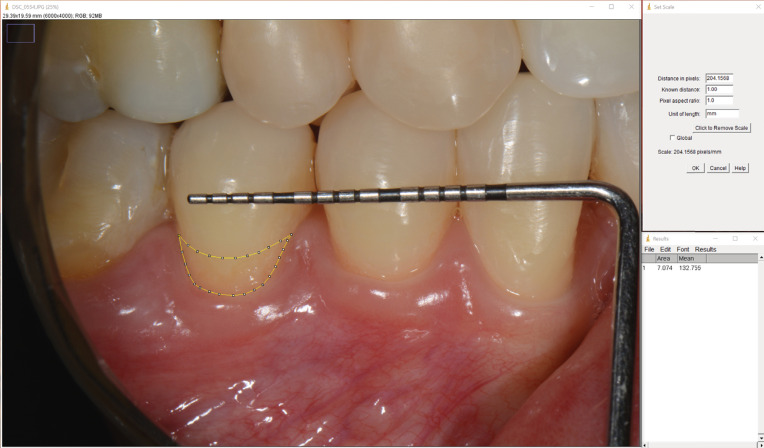

牙本质过敏(DH)是一种常见且具有挑战性的临床疾病,长期治疗有限。本研究的目的是评估980 nm二极管激光治疗DH的有效性,是否与氟化物清漆相关。选择60名志愿者,随机分配接受三种不同的治疗方案(1- 0.8W二极管激光治疗;2-用0.8 W二极管激光在氟化物清漆上处理;或仅限3氟清漆)。0.8 W二极管激光以10 Hz的频率照射暴露根部,照射时间为30 s,能量密度为99.17J/cm2,呈锯齿形。分别在治疗前、治疗后、治疗后7天、30天和180天采用视觉模拟量表(VAS)进行DH评估。获得的数据进行双向重复测量方差分析(ANOVA) (p

Dentin hypersensitivity (DH) is a common and challenging clinical condition with limited long-lasting treatments. The objective of this study was to evaluate the effectiveness of 980 nm diode laser treatment, associated or not with fluoride varnish, in the treatment of DH. Sixty volunteers were selected and randomly assigned for treatment following three different protocols (1- treatment with 0.8W diode laser; 2- treatment with 0.8 W diode laser over fluoride varnish; or 3- fluoride varnish only). The 0.8 W diode laser was applied in contact with the exposed roots at 10 Hz, for 30 s, with 99.17J/cm2 energy density, using a zigzag pattern. DH assessment was performed using the visual analog scale (VAS), prior to treatment, immediately after treatment, and at 7, 30, and 180 days after treatment. The data obtained were subjected to two-way repeated-measures analysis of variance (ANOVA) (p <0.05). The varnish group showed a reduction in DH up to 30 days, whereas the laser and laser + varnish groups showed a reduction in DH up to 180 days ,with no difference between them. The laser and laser + varnish groups were superior to the varnish group after 30 days. The treatment of exposed roots with diode laser alone or associated with fluoride varnish, according to the parameters used in this study, was effective in reducing DH up to six months.